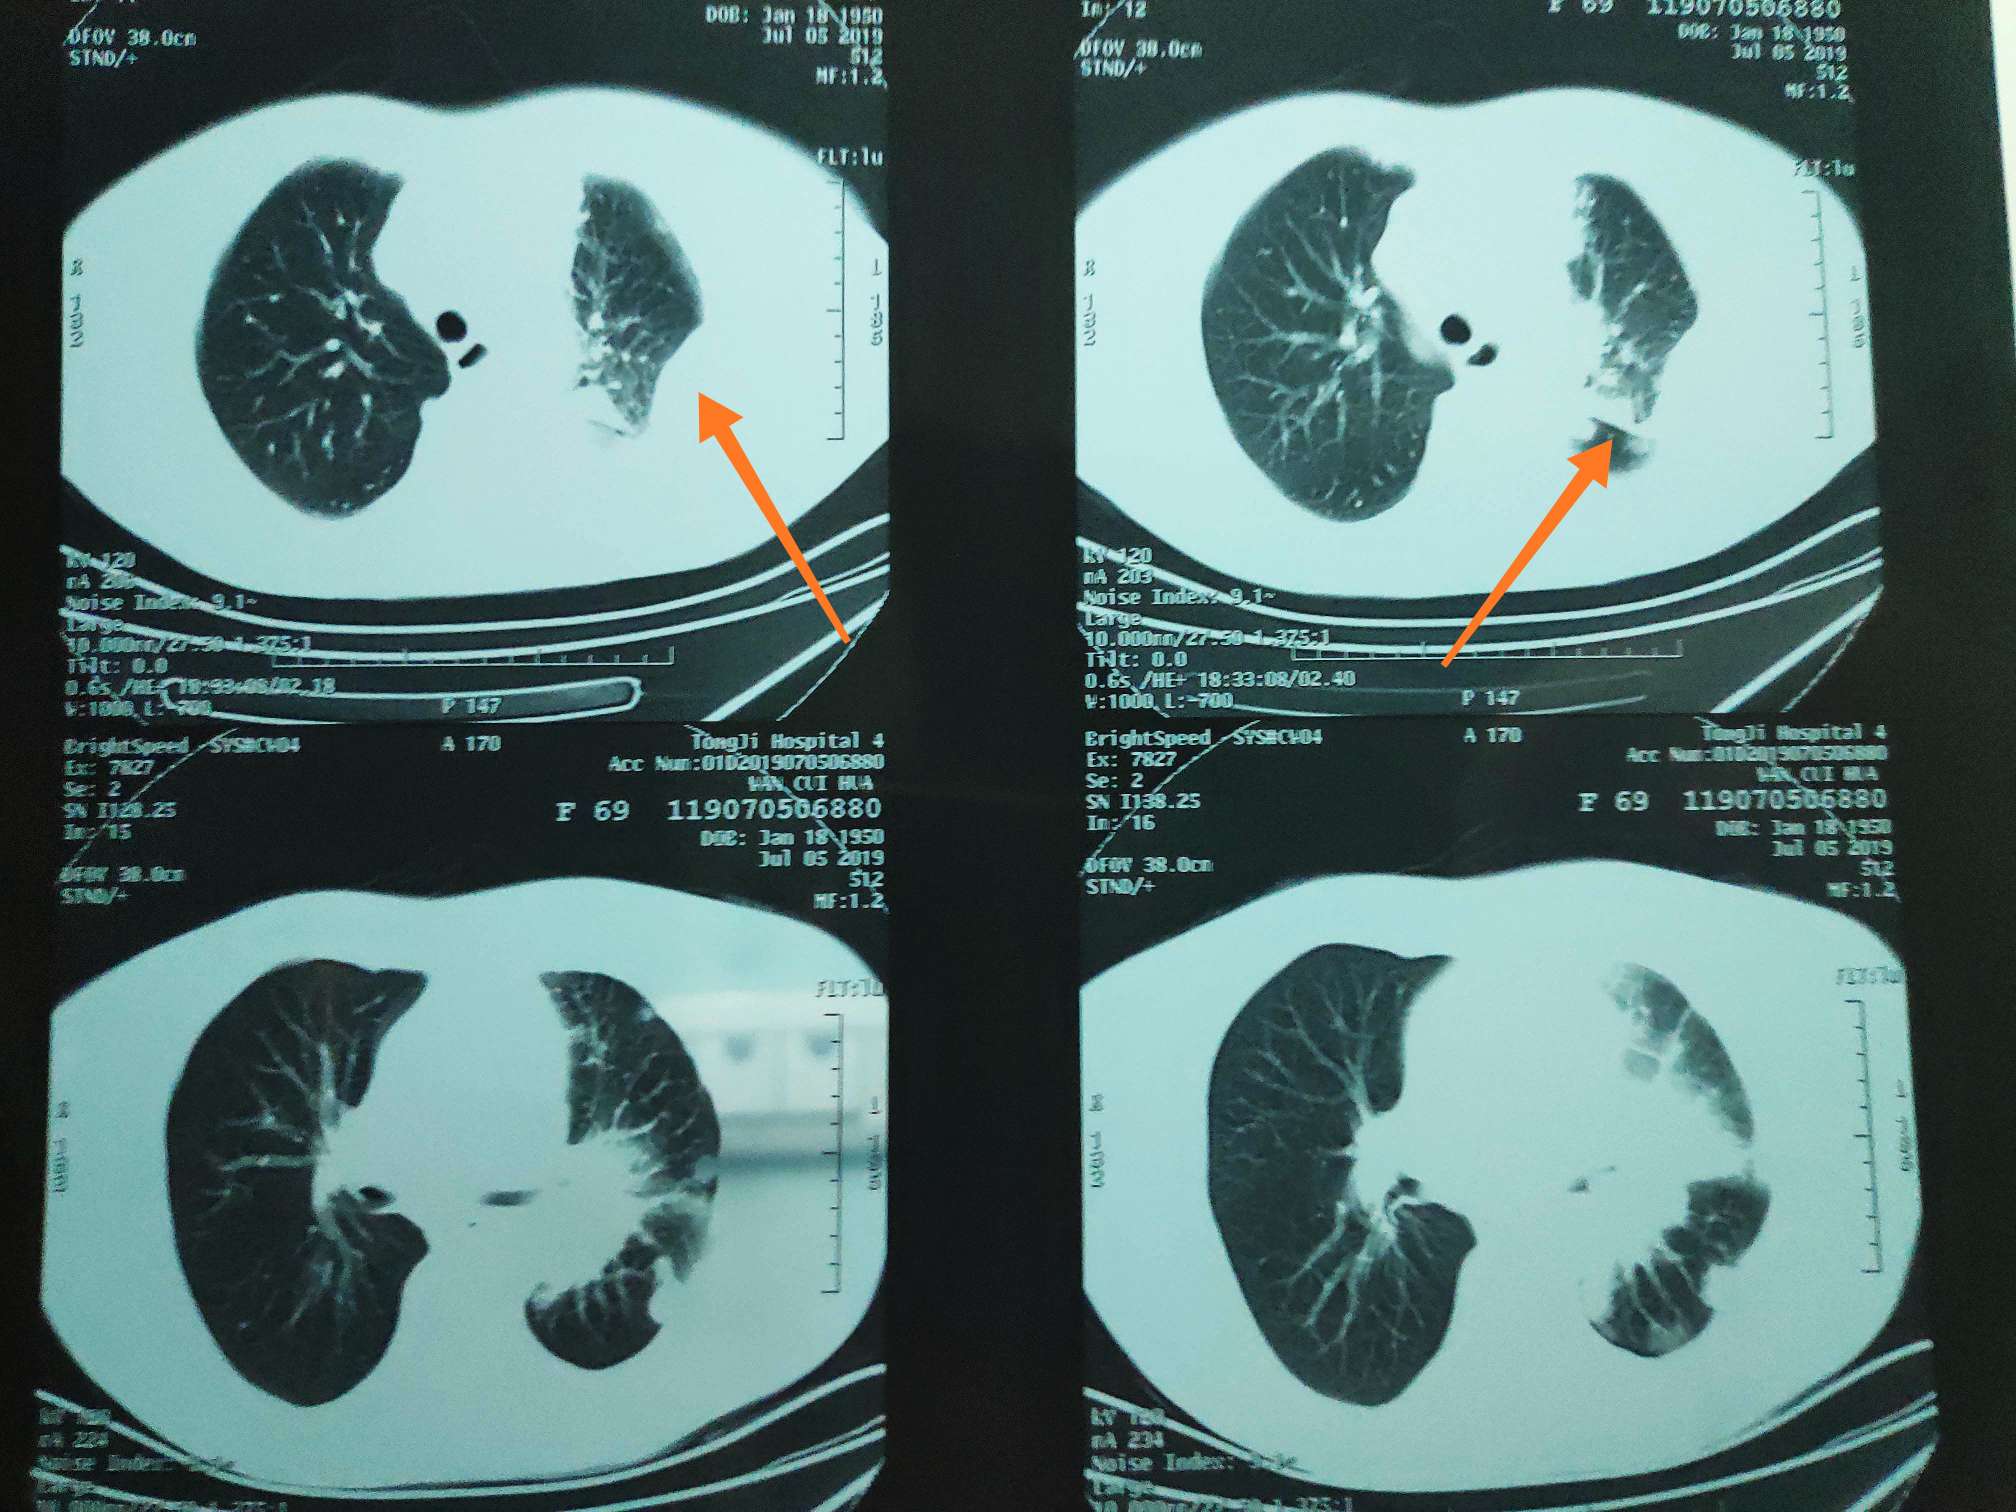

7月5日一化前CT检查,

一化前CT